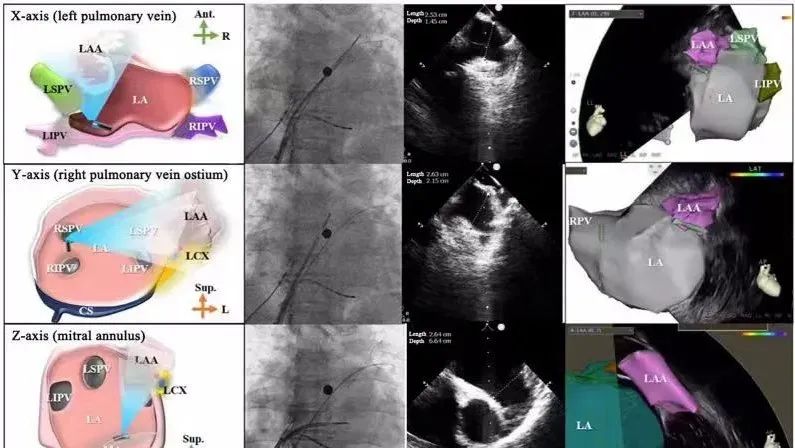

一種與心導(dǎo)管檢查相結(jié)合的超聲心動(dòng)圖診斷新興技術(shù),通過將超聲探頭置于心腔內(nèi)部,發(fā)射并接收超聲信號(hào),來精確獲取心臟解剖結(jié)構(gòu)、心臟血流動(dòng)力學(xué)等信息的實(shí)時(shí)成像。與其他影像技術(shù)相比,ICE技術(shù)具有操作簡單、無輻射、安全性高、手術(shù)效率高、實(shí)用等優(yōu)勢,ICE在很大程度上有望取代經(jīng)食道超聲心動(dòng)圖(TEE),成為電生理和結(jié)構(gòu)性心臟病領(lǐng)域的理想成像方式。

心腔內(nèi)超聲(ICE)技術(shù)壁壘極高,國內(nèi)主要廠商核心部件仍舊為進(jìn)口,集成了超聲和圖像處理最前端技術(shù),包括超聲探頭、線纜、軟件成像算法等,是當(dāng)前內(nèi)窺超聲方向最具挑戰(zhàn)的領(lǐng)域。ICE的應(yīng)用經(jīng)歷了2D平面成像、3D三維立體成像、以及4D的實(shí)時(shí)三維立體成像階段。